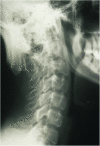

Menkes disease (MD) is a lethal multisystemic disorder of copper metabolism. Progressive neurodegeneration and connective tissue disturbances, together with the peculiar 'kinky' hair are the main manifestations. MD is inherited as an X-linked recessive trait, and as expected the vast majority of patients are males. MD occurs due to mutations in the ATP7A gene and the vast majority of ATP7A mutations are intragenic mutations or partial gene deletions. ATP7A is an energy dependent transmembrane protein, which is involved in the delivery of copper to the secreted copper enzymes and in the export of surplus copper from cells. Severely affected MD patients die usually before the third year of life. A cure for the disease does not exist, but very early copper-histidine treatment may correct some of the neurological symptoms.